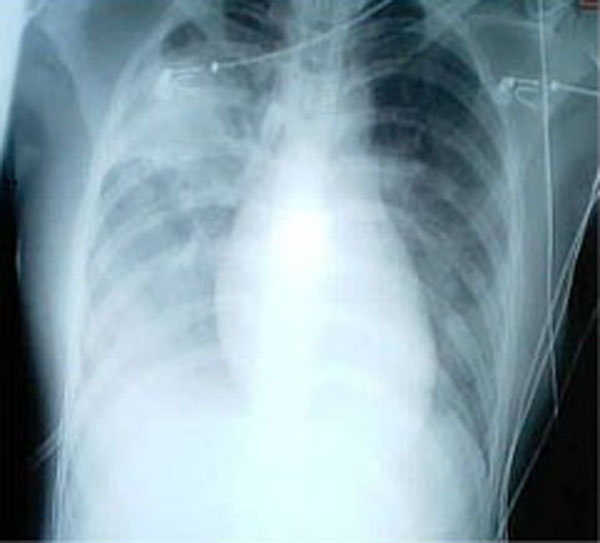

사스 의심 사례는 38℃ 이상의 발열과 더불어, 사스 확진자와의 접촉력, 세계보건기구(WHO) 지정 사스 발생 국가 방문력 등의 요소를 종합하여 판단한다. 흉부 X선 촬영에서 이상 소견이 발견되면 사스 가능성이 높은 것으로 간주된다.

임상 증상은 인플루엔자나 마이코플라스마 폐렴과 유사하여 증상만으로는 감별하기 어렵다[99]. 초기에는 X선 사진에서 기도 염증 소견을 보이지 않으며[99], 흉부 X선 사진 소견은 항상 균일하지 않지만 일반적으로 부분적인 침윤으로 이상 소견이 나타난다.[13]

위 조건을 만족하고 흉부 방사선 사진상 이상 증상이 보이면 중증 급성 호흡 증후군 가능성이 높다. 확진을 위해서는 사스-코로나 바이러스를 세포 배양하여 분리하거나 역전사 중합효소 연쇄반응(RT-PCR)법을 이용하여 바이러스 핵산을 검출해야 한다.[97]

현재 증례 정의는 여행 경험을 묻지 않고, 38도 이상의 고열 및 기침, 호흡 곤란, 숨가쁨 중 하나 이상의 증상을 보이고, X선 검사에서 폐렴 증상이 있으며 원인이 불분명하고 바이러스 검사에서 양성인 경우이다.

감염 의심이 짙은 환자는 흉부 X선 사진에서 비정형 폐렴이나 급성 호흡 부전 증후군 등의 증상, 또는 코로나바이러스 검사에서 양성 소견이 나타난다.